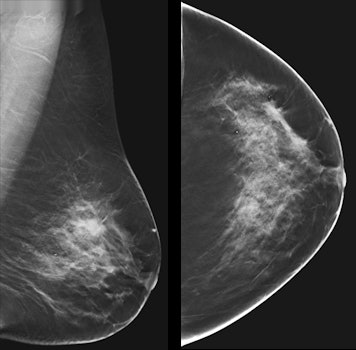

3. DBT debate: Can it replace screening mammography?

Digital breast tomosynthesis (DBT) has its legion of fans who cite its ability to increase cancer detection and reduce false-positive rates. So is the technology ready to replace digital mammography for screening?

"It's the most promising tool we have," said breast imaging pioneer Dr. Sylvia Heywang-Köbrunner of Breast Diagnostics Munich in a symposium dedicated to breast health.

DBT's potential can't be denied and its superior sensitivity when compared to digital mammography isn't in doubt, she asserted.But a number of issues need further study, including whether DBT is finding clinically important cancers, the logistics of incorporating the technology into department workflow, and reducing reading time -- which can be two to four times longer than digital mammography.

As well, data on DBT's performance with interval cancers is lacking.

"Tomosynthesis is the better modality when compared to digital mammography," saidHeywang-Köbrunner. "But is it ready now to replace [2D mammography] for screening? No. We're lacking information, particularly about its interval cancer performance."

Research highlighted at the meeting from the Swedish Malmö breast tomosynthesis screening trial underlined the same concerns, although presenter Dr. Kristina Lång, PhD, of Lund University suggested that DBT is more ready than not for screening primetime -- especially with help from artificial intelligence to address the reading time problem. In any case, her team plans to work with researchers from the Screening with Tomosynthesis or Standard Mammography (STORM) trials and the Oslo Tomosynthesis Screening Trial (OTST) to tackle the interval cancer issue. Once that's resolved, screening DBT will be ready to replace digital mammography.

"Breast tomosynthesis increases the cancer detection rate in screening with a reasonable elevation of the recall rate," Lång said. "When interval cancer data has been analyzed, [we'll be able] to use tomosynthesis for screening -- with the aid of artificial intelligence."

While the screening question continues to be debated, DBT is proving to be a valuable tool for a variety of other applications, including staging surgical breast cancer treatment, researchers from Turin, Italy, reported. They found that, when used with digital mammography, DBT cut the re-excision rate in women who underwent breast cancer surgery by half compared to those who were staged with digital mammography and ultrasound: from 10% to 5%.